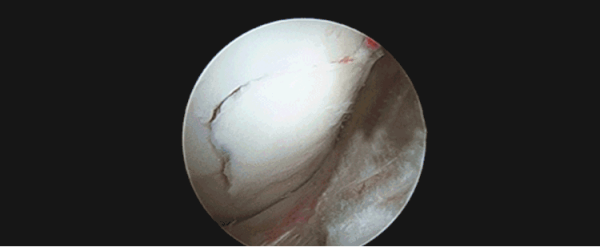

膝关节半月板损伤导致关节软骨磨损

关节软骨损伤

年轻时膝盖受过伤,是老年后骨关节炎发生的主要原因之一。膝关节结构复杂,伤情也复杂,但无论是骨软骨损伤、半月板伤还是韧带伤,不及时处理都可能带来严重的后果。